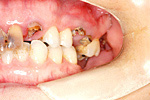

症例 6

① 虫歯でぼろぼろの歯は抜きます。

② 歯の無いところはインプラントで補います。

60才代 女性

総額:300万円(税別)

治療期間:1年6ヵ月

リスク副作用:清掃不良ですと歯周痛が再発します。セラミックが欠けることがあります。